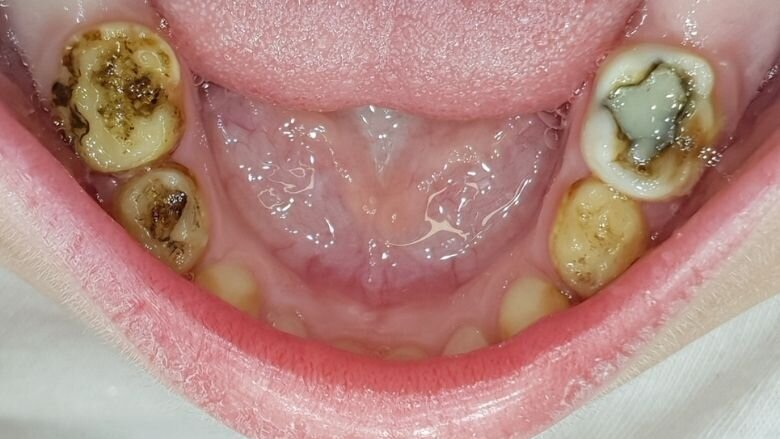

Een kind van vierenhalf jaar met multi-cariës werd verwezen voor behandeling onder narcose (afb. 6a-e). Klacht: lichte gevoeligheid .

Bij deze eerste sessie trainde ik het poetsen, opende ik de laesies voorzichtig en behandelde de laesies met SDF. Bij het monitoren zal blijken of er aanvullende behandelingen nodig zijn zoals herhalen SDF, SMART, Hall-kroon of lokaal een conventionele behandeling.

Het kind ging glimlachend weg. De ‘brandhaard’ in haar mond was gedoofd. Er bestaan inmiddels zoveel kindvriendelijke mogelijkheden om tanden vitaal te houden, waarom zouden we die afwijzen?Het lijkt me dat deze benadering zoveel logischer is dan wat ik de in voorafgaande dertig jaar deed. Ook bij patiënten met een handicap pas ik narcose veel minder vaak toe dan in het verleden.

Afbeelding 6a. Multi-cariës bij intake.

Afbeelding 6b. Multi-cariës bij intake.

Afbeelding 6c. Multi-cariës bij intake.